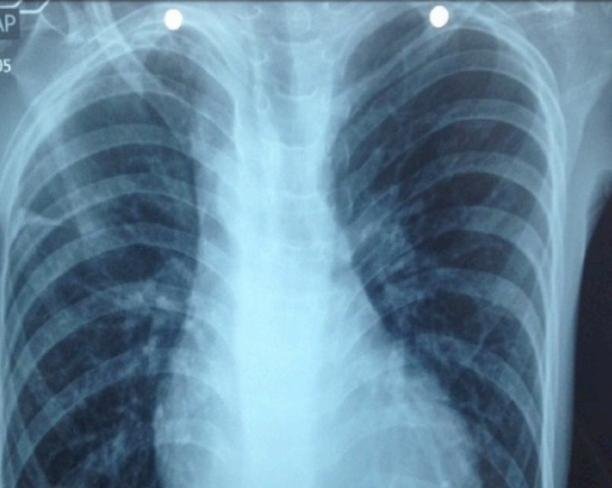

Cardiopatia congênita (provavelmente tetralogia Fallot)

Vamos analisar: temos desnutrição, baqueteamento digital, poliglobulia maciça, sopro sistólico e arco aórtico á direita. São sinais patognomônicos para hipoxia cronica causada por algum defeito cardíaco. Cardiopatias congênitas são anomalias do aparelho circulatório presentes desde o nascimento, sendo divididas em cianóticas e acianóticas. A Tetralogia de Fallot é a cardiopatia cianótica mais comum, caracterizada por comunicação interventricular, estenose subpulmonar, origem biventricular da valva aórtica e hipertrofia ventricular direita. O diagnóstico costuma ser realizado no primeiro ano de vida devido às manifestações clínicas precoces, na maioria dos casos. Contudo, em alguns casos, a associação de outras malformações cardíacas e falhas no sistema de saúde podem contribuir para realização de diagnósticos tardios, aumentando a probabilidade de prognósticos desfavoráveis.